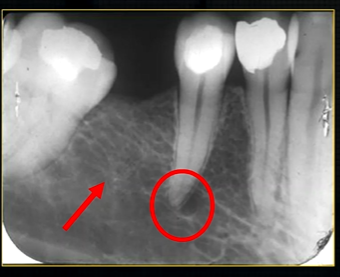

mental foramen - black radiolucency - near 1st and 2nd premolars

radiolucent band around the posterior part of the body of the mandible

created by inferior dental nerve and blood vessel, created by the inferior dental canal

the edges of the canal can be seen as thin, white radiopaque lines → ‘tram lines’

inferior dental canal can easily be seen in cross sectional dental images